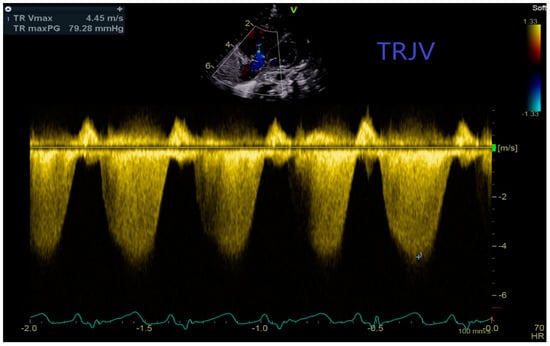

| TPV/RVET | Time To Peak Velocity/Right Ventricular Ejection Time Ratio |

| TRJV- | Tricuspid Regurgitant Jet Velocity |